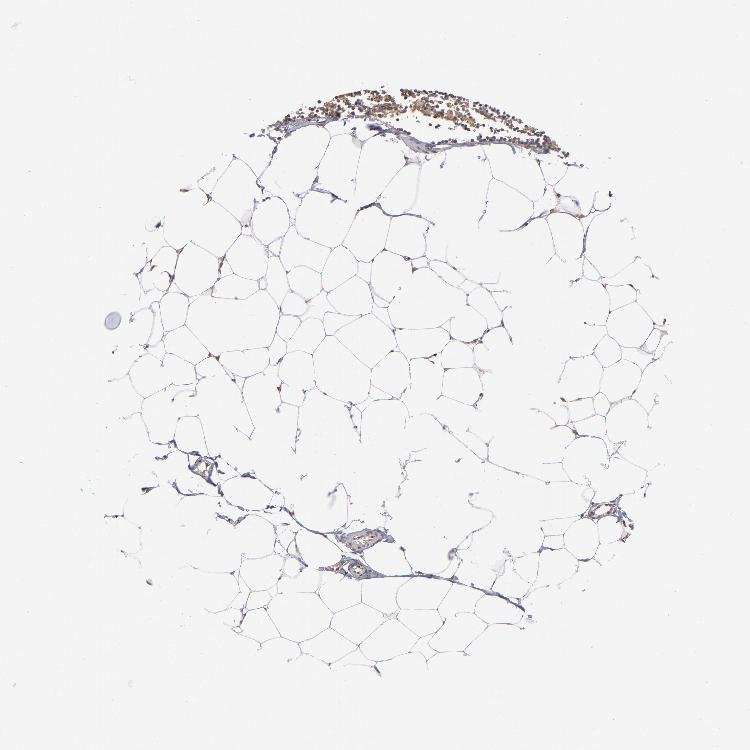

ADIPOSE TISSUE - Antibody stainingi

Antibody staining in the annotated cell types in the current human tissue is reported as not detected, low, medium, or high, based on conventional immunohistochemistry profiling in selected tissues. This score is based on the combination of the staining intensity and fraction of stained cells.

Each image is clickable and will lead to virtual microscopy that enables deeper exploration of all samples and also displays staining intensity scores, fraction scores and subcellular localization as well as patient and tissue information for each sample.

Antibody HPA002548Antibody CAB022718

Adipocytes Not detectedLow